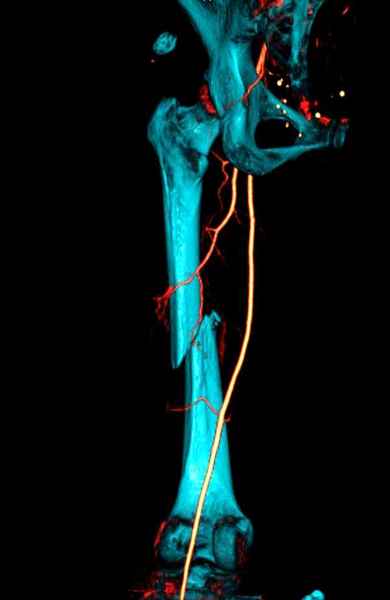

Для предупреждения кровотечения во время рассверливания, за день до операции провели эмболизацию сосудов питающий метастаз. http://radiology.rsnajnls.org/cgi/reprint/150/3/673.pdf (7-11, 12-15-16)

С минимальным рассверливанием и ретроградным методом провели остеосинтез бедра 12 мм гвоздем. (17-20)